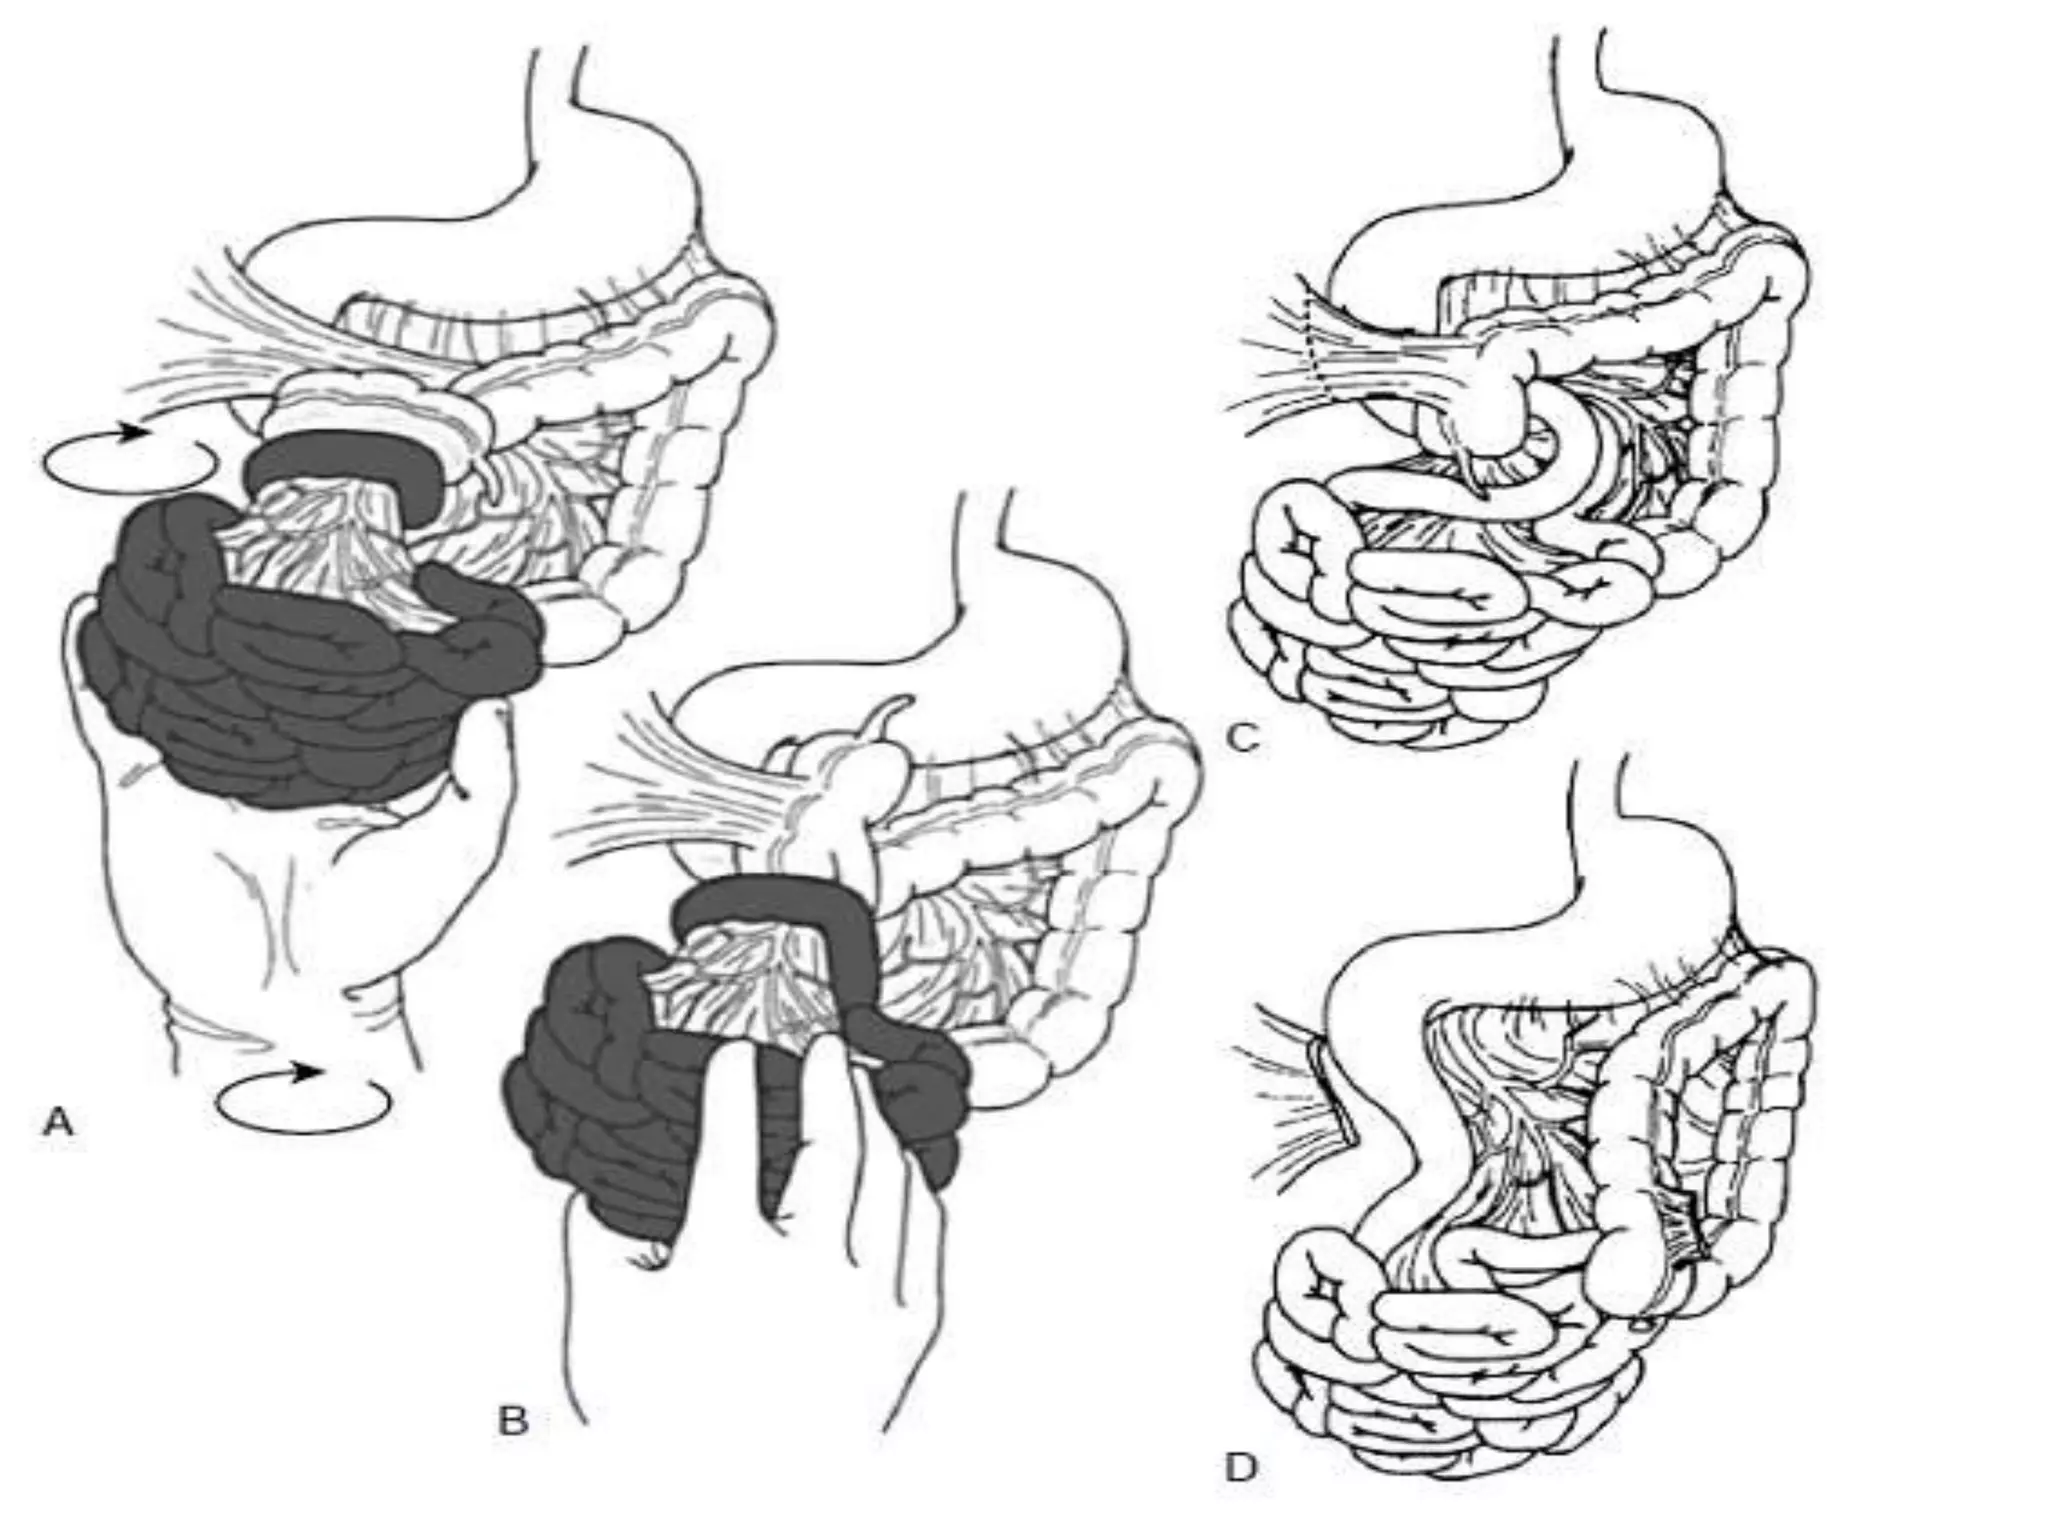

Treatment:

(ladd’s procedure)

• The aim of surgery:

• 1. Entry into abdominal cavity and evisceration

(open)

• 2. Counterclockwise detorsion of the bowel

(acute cases)

• 3. Division of Ladd’s cecal bands

• 4. Broadening of the small intestine mesentery

• 5. Incidental appendectomy

• 6. Placement of small bowel along the right

lateral gutter and colon along the left gutter

Treatment: (ladd’s procedure) • Theaim of surgery: • 1. Entry into abdominal cavity and evisceration (open) • 2. Counterclockwise detorsion of the bowel (acute cases) • 3. Division of Ladd’s cecal bands • 4. Broadening of the small intestine mesentery • 5. Incidental appendectomy • 6. Placement of small bowel along the right lateral gutter and colon along the left gutter